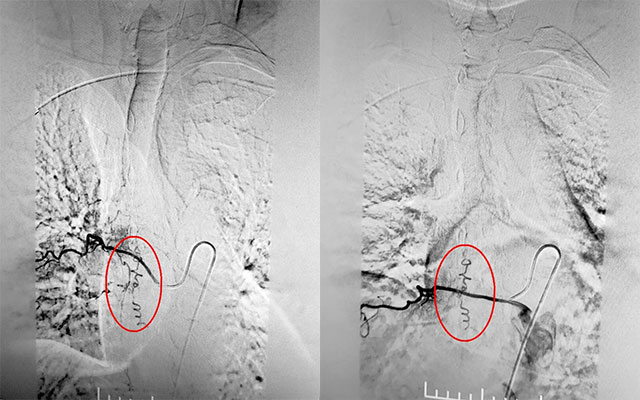

▲ DSA確診硬脊膜動(dòng)靜脈瘺

為了定位病灶,3月16日下午1點(diǎn),在復(fù)合手術(shù)室,張琪博士在劉春醫(yī)生、周林華醫(yī)生協(xié)助下通過股動(dòng)脈穿刺術(shù)將造影劑推入各個(gè)脊髓間動(dòng)脈。需要一條動(dòng)脈一條動(dòng)脈的試,并且脊髓間動(dòng)脈復(fù)雜,需要非常細(xì)致的手法,十分考驗(yàn)醫(yī)生的細(xì)心與耐心。經(jīng)過兩個(gè)多小時(shí)的連續(xù)造影,終于在T8右側(cè)肋間動(dòng)脈發(fā)現(xiàn)瘺口。“造影提示,該處瘺口由肋間動(dòng)脈供血至硬脊膜靜脈,脊髓引流靜脈迂曲擴(kuò)張明顯。”張琪博士解釋道。